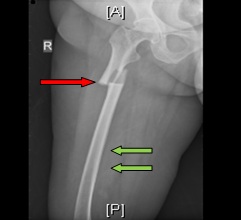

An anteroposterior left femur radiograph showing a transverse shaft fracture, with a localized periosteal beaking (red arrowhead) and generalized cortical thickening (green arrows)

An anteroposterior right femur radiograph showing an incomplete atypical shaft fracture with a periosteal reaction of the lateral cortex